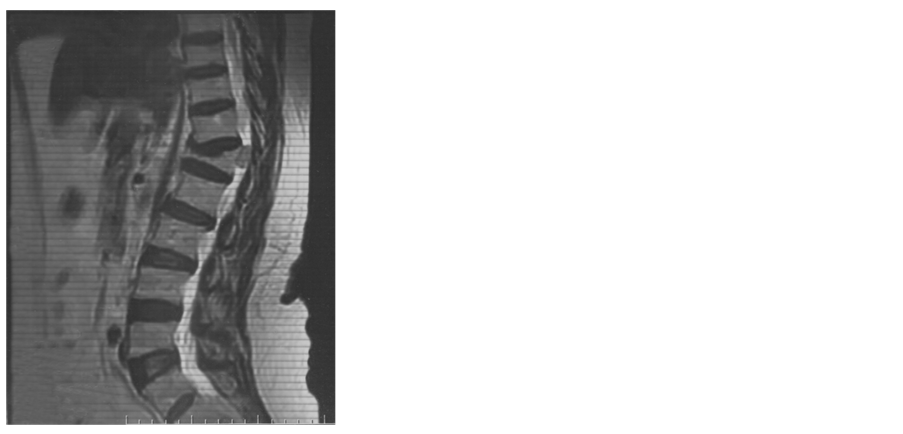

A 61-year-old female patient was with history of spinal trauma in 26 year ago. Patient fall down from height and had a traumatic L1 fracture. Patient was managed conservatively at that time as she refused surgical intervention and had no neurological deficit. Patient experienced frequent attacks of low back pain and rarely sciatic pain that was treated with analgesia. 6 months ago, the patient had a progressive heaviness in both lower limbs with urinary incontinence and visited the outpatient clinic. On examination, the patient was paraparetic with motor power grade II or III below L1. Patient had hypotheisa below L1 with diminished knee and ankle reflexes. MRI lumbar and dorsal spine showed the post-traumatic L1 fracture with a new large intra-dural mass most probably meningioma or schwnoma as shown in Figure 1. Patient operated with posterior lumbar approach including posterior L1 and D12 laminectomy. Total standard microscopic excision of the intra-dural soft tissue mass with moderate vascularity was performed successfully. A posterior D11, D12 and L2 trans-pedicular screw fusion was performed at the end of the procedure. Histopathological examination revealed multiple nodules of proliferated meningothelial cells separated by delicate fibrous tissue, with thick walled blood vessels and calcified psammoma bodies together with oval to rounded cells with oval nuclei, occasional nuclear clearing and infrequent mitosis arranges in whorly pattern with rounded calcified psamma bodies. A meningeothelial and psamomatous meningioma was reported as shown in Figure 2. The patient has smooth postoperative course with improvement of her neurological deficit with physiotherapy. 4 months after surgery, the patient was able to ambulate without assistance. On her last follow up after one year of surgery; the patient has no neurological deficit and can ambulate without assistance

Figure 1. (a) X ray lateral view shows L1 fracture; (b) X ray anteroposterior view shows L1fracture; (c) MRI lumbosacral spine T2 weighted image sagittal view shows the L1 fracture and the intradural mass; (d) MRI lumbosacral spine T1 weighted image sagittal view shows the L1 fracture and the intradural mass; (e) MRI Dorsal spine T2 weighted image sagittal view shows the L1 fracture and the intradural mass; (f) MRI lumbosacral spine T2 weighted image axial view shows the intradural mass compressing the cord; (g) X ray lateral view shows the pedicular screws; (h) X ray anteroposterior view shows the postoperative fusion.